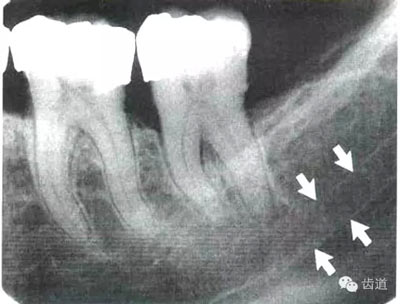

牙頸部Burnout征象:有時(shí)因投照技術(shù)問(wèn)題而造成牙頸部近中或遠(yuǎn)中呈低密度影像,位于牙釉質(zhì)和牙槽嵴頂之間。